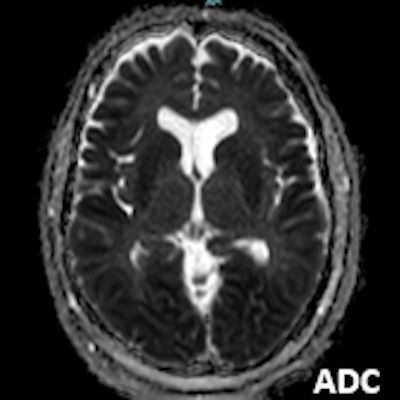

- A) Bilateral serebral kortekste (oklar) ve bazal ganglionlarda (oklar) yaygın DAG hiperintens, ADC hipointens difüzyon kısıtlamaları görülüyor.